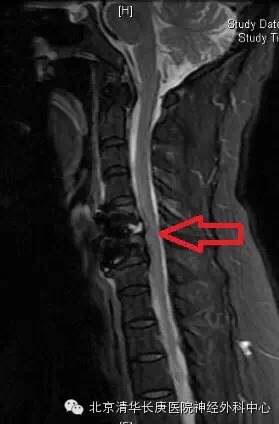

CT显示:C5-6,6-7椎间盘突出,后纵韧带骨化

术后MRI:C5-6突出椎间盘消失